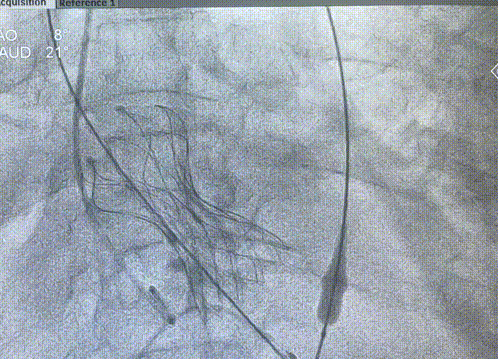

图片

术后主动脉弓部造影,未发现夹层

最终结果

术后患者测得左室压力137/12mmHg,主动脉根部压力131/49mmHg。平均跨瓣压差由术前约59mmHg,改善至术后约6mmHg

最终,在整个手术团队通力合作,血管外科同事的帮助下,过弓顺利、定位精准,一次性释放成功,术后轻度瓣周漏,手术跨瓣压差均稳定在6mmHg,完美的完成了TAVR手术。